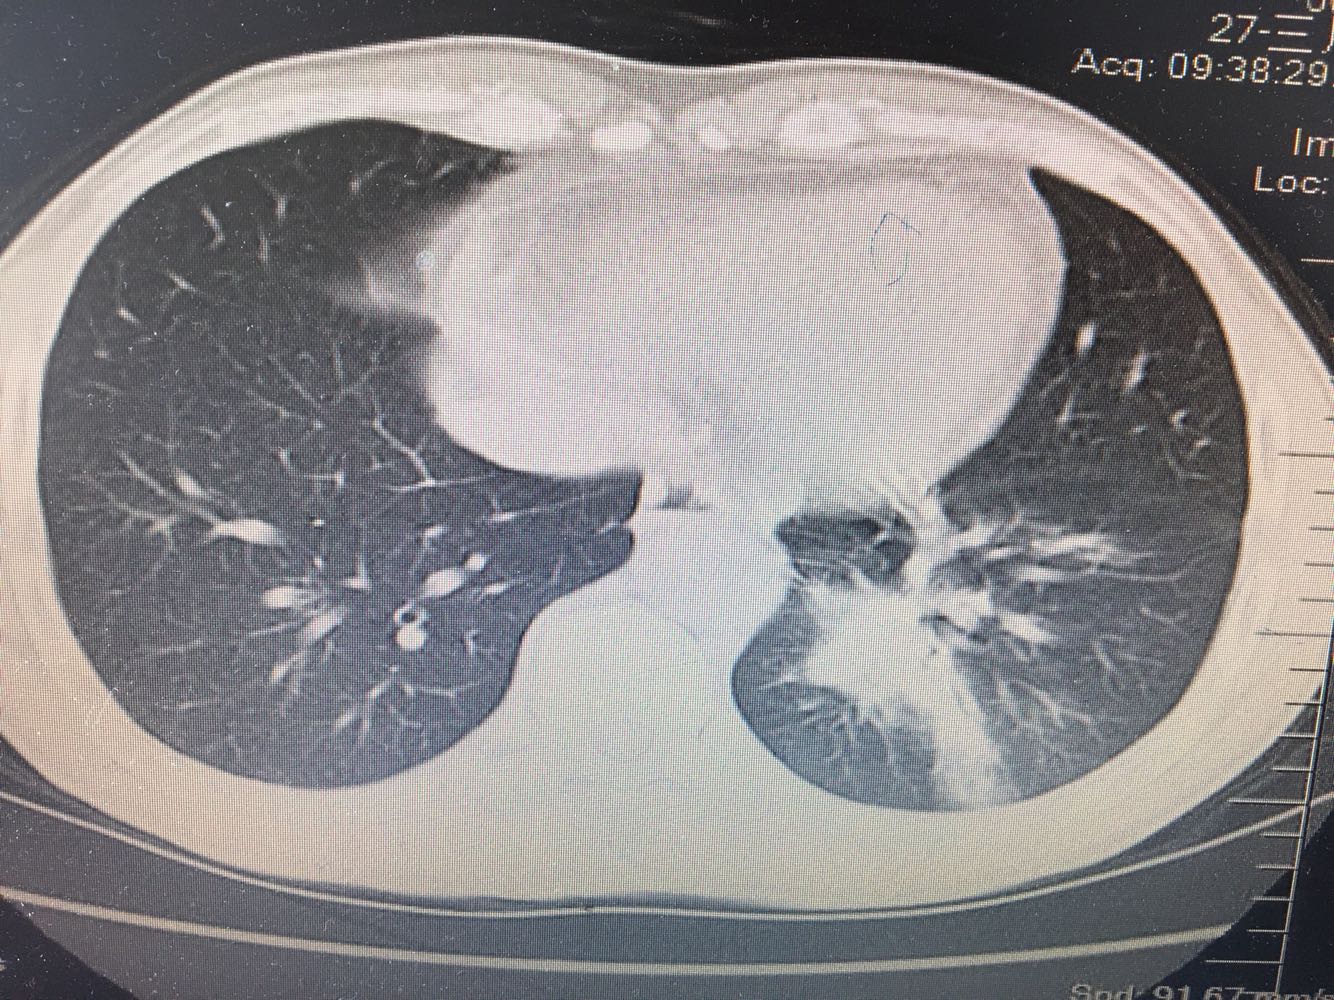

左肺下叶鳞癌

男,63岁,咳嗽1个月入院,患者自述1个月前无诱因咳嗽,阵发性干咳,无痰,时有血丝,无发热,左胸痛,活动后气短,静滴头孢13天无好转,门诊查肺CT后以 肺占位收入我科,病来饮食睡眠可,体重明显下降。既往疝气术后1年,吸烟史30年,每日1包。

左肺癌

左肺中央型肺癌,是否可以手术,还是化疗,放疗,靶向治疗?